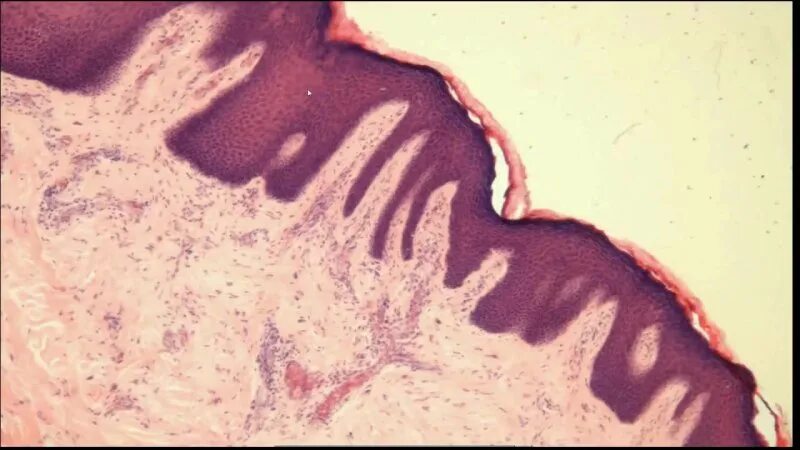

Твердое небо гистология